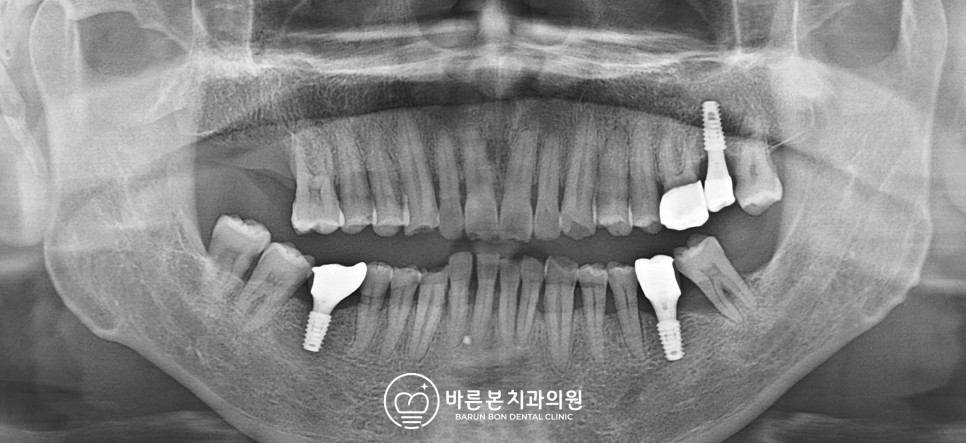

<22.03.29 촬영> 먼저 비어있던 부분에 식재가 끝났습니다.

이후 임플란트 치료를 위해 (1) 통증이 느껴지는 17번 발치(2) 기존 발치가 이루어진 27번, 36번, 46번 임플란트 식립을 시행하였습니다.

기존 치아 상태가 좋지 않아 인공치아의 형태를 안정적으로 갖추기 위해 #28, #37, #48의 발치를 권장하였으나 아직 좀 더 사용하고 싶어 추후 상태가 더 나빠지면 치료하기로 하였습니다.